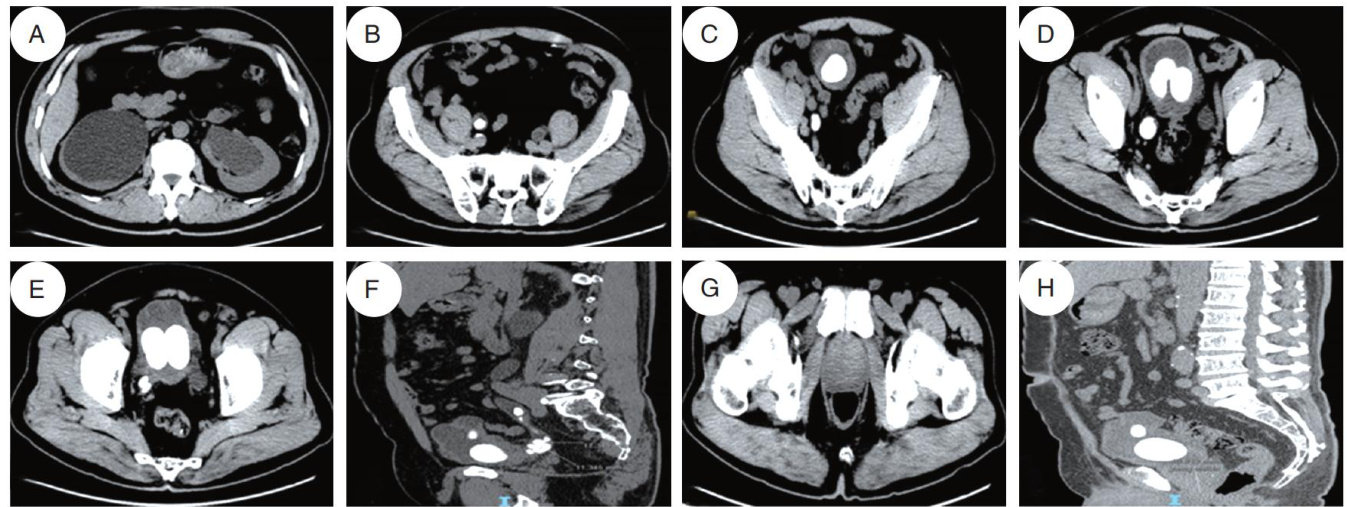

摘要目的:分析机器人辅助置钉联合矫形术后脊柱侧弯患者肺部并发症影响因素并探讨相应的管理策略。方法:选取2022年1月—2024年3月于清华大学附属北京清华长庚医院接受机器人辅助置钉联合矫形术治疗的103例脊柱侧弯患者为研究对象。根据患者术后2个月内是否出现肺部相关并发症分为发生组( n=17 )和未发生组( n=86 )。比较两组基础人口学资料、病情资料以及手术资料,Logistic单因素及多因素分析脊柱侧弯患者经机器人辅助置钉联合矫形术治疗后肺部并发症影响因素,建立受试者工作特征(ROC)曲线评估影响因素预测效能,根据影响因素探讨相应的管理策略。结果:与未发生组相比,发生组营养不良、卧床时间 ?1 周占比更高,白细胞计数水平更高,手术时间更长( P<0.05 )。单因素Logistic回归分析显示营养状况、卧床时间、白细胞计数、手术时间为患者肺部相关并发症发生的影响因素( P<0.05 )。多因素Logistic回归分析显示营养不良、白细胞计数高及手术时间延长会增加患者肺部相关并发症发生风险( P<0.05 )。营养状况、白细胞计数、手术时间单独及联合预测曲线AUC分别为 0.708,0.857,0.748,0.941 。结论:营养不良、白细胞计数高及手术时间延长会增加患者肺部相关并发症发生风险,临床需优化术前评估及术后管理方案以预防术后肺部并发症。